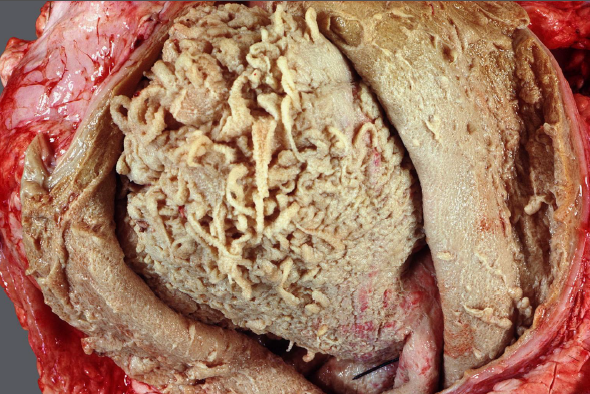

Rind, Herz/Trikuspidalklappe: Hochgradige, chronisch-aktive, multifokale, fibrinös-eitrige Endocarditis valvularis

Beschreibung:

auf der Trikuspidalklappe lassen sich multiple, blumenkohlartige Verdickungen, sowie Aufrauungen und Ulzerationen

des Klappenendothels darstellen.

Es sind dunkelrot-gelbe, unregelmäßig geformte

Fibrinauflagerungen auf und zwischen den Verdickungen zu erkennen

Hintergrundwissen/ Infektionsweg/ Pathogenese

prinzipiell bei allen Tieren, am häufigsten betroffen sind Rind (Trikuspidalis) und Schwein (Mitralis), selten bei Hund (Mitralis) und Pferd (Aortenklappe)

selten vollständige Regeneration, durch Strömung und mechanische Kräfte eher sich selbst erhaltender Entzündungsprozess, intraläsionale Bakterien sind nicht immer nachweisbar

Infektionswege/Pathogenese:

genauer Mechanismus bislang nicht vollständig geklärt (evtl. Vorschädigung durch Traumata, Sepsis, Arbeitsüberlastung)

Folge einer bakteriämischen Infektion, Endothelschäden (z.B. bakteriell-toxisch) und Thrombusbildung (i.S. Virchow-Trias)

Anhaftung an den Klappen i.F. von begünstigenden Strömungsverhältnissen und spezifischer Bakterien-Endothel-Wechselwirkung (z.B. Erysipelothrix rhusiopathiae)

Vegetativer (d.h. veränderlicher) Entzündungscharakter, fibrinös-eitrige Charakteristika gehen z.B. mit steigender Chronizität in eitrig-granulierende über

Erreger (exemplarisch):

Trueperella pyogenes (Rd.), E. rhusiopathiae (Schw.), Streptococcus spp., Staphylococcus spp. (Flfr. & Pfd.)

Komplikationen:

Mitralis: Thrombembolien (Niereninfarkte, embolisch-eitrige Herdnephritis, Stauungslunge); Trikuspidalis: Lungenembolie, embolisch-eitrige

Pneumonie, Aszites, Stauungsleber

DD für Herzklappenveränderungen: Endokardiose (Hd.), Klappenzysten, Klappenamyloidose (Rd.)